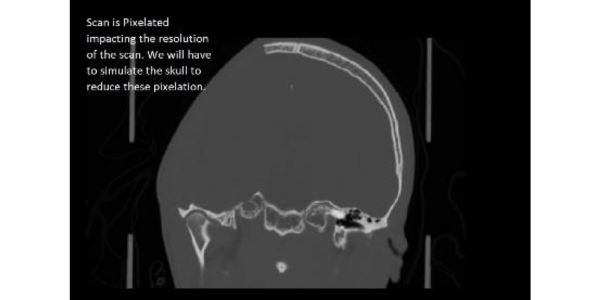

He underwent emergency decompressive craniectomy on the same day. However, the patient's bone flap, which had been temporarily stored in the abdomen, was

found to be unsuitable due to fragmentation. Consequently, the decision was made to proceed with a cranioplasty using a customized 3D printed PEEK (Polyether Ether Ketone) implant under general anesthesia.